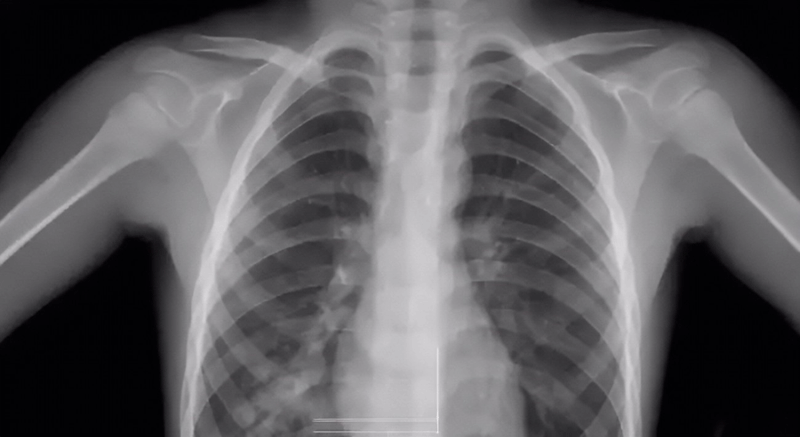

1 胸透检查方式

胸透的检查方式是利用X射线的穿透性、荧光性和摄影效应等特性,使患者的肺部等在荧屏上形成影像。由于人体组织有密度和厚度的差别,所以当X射线穿透人体时,X线被不同程度的吸收了,到达荧屏上的X射线量就有差异,然后形成黑白对比明显的成像,为医生的诊断提供依据。

关于胸透检查报告

做胸透检查可以查出的项目非常多,它是通过X射线穿透人体的不同层度结合荧光成像来分析人体某部位存在的异常。胸透检查报告的主要内容有:显示肺部是否有疾病、心脏是否有异常、胸膜有无问题、胸壁纵隔、肋骨有无受损、支气管疾病等。

胸透检查结果要仔细分析才能懂

胸透检查报告常见结果分析:

1、两肺未见明显活动性病变:说明肺部非常健康,无病变出现;

2、胸廓无异常,两肺纹理清晰:说明胸部或肺部没有任何异常;

3、两上肺可见斑点状钙化:说明患者以前可能在不知情的情况下得过结核病,但没有发现就自愈了;

4、两肺门影不大:说明肺部和器官都很健康,心脏功能也很正常,若有心脏病,可能会引起肺门水肿;

5、气管、纵隔无偏移:说明颈部和胸腔内没有出现肿瘤或任何异物,如果有肿瘤或异物的话会把气管和纵隔推偏,看起来位置就会发生错位;

6、两肋膈角锐利:说明胸腔内没有积水或渗出液,当出现炎症或结核等病变时会引起积液渗入到胸腔内,使肋膈角变得模糊圆钝;

7、心影形态大小未见明显异常:说明心脏是健康的;

8、膈面光整:腹腔里面的各个小组织没有出现穿孔,因为穿孔会让气体外泄,使膈面下有黑影。